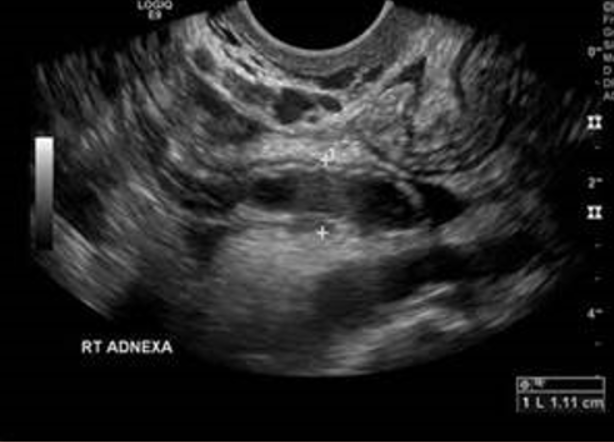

Acute appendicitis